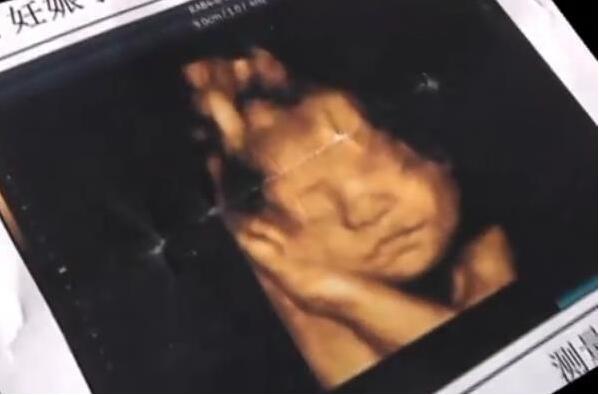

图为彩超婴儿影像。